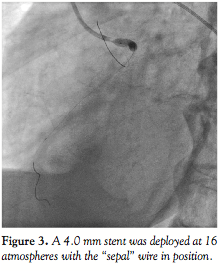

was thus achieved. This also allowed good contrast filling for visualization of the anatomical relationship (Figure 2). The 4.0 mm stent was deployed at 16 atmospheres (Figure 3). Final angiography showed excellent results (Figure 4), with the guiding catheter engaging easily into the LM after removal of the “sepal” wire. IVUS confirmed excellent ostial stent coverage (Figure 5).